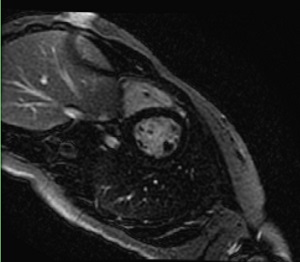

Figure 1. 2D multi-slice single breadth hold Single Shot Delayed Enhancement images